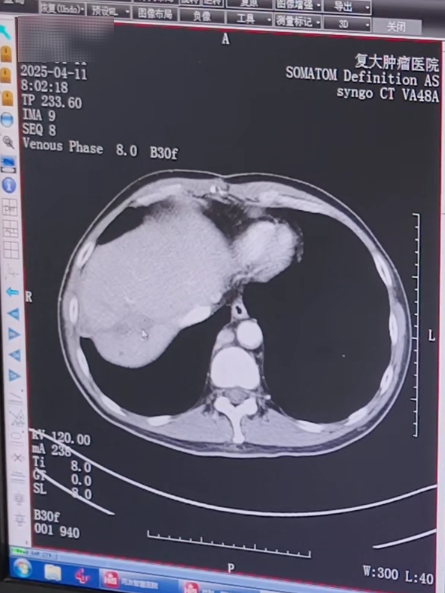

كان العم وانج، الذي دخل المستشفى للتو، يعاني من آفة نقيلية كبيرة في الفص الأيمن من الكبد، وكان حجمها تقريبًا 7.4×6.7×9.2 سم. كانت هناك العديد من العقد الليمفاوية الصغيرة في منطقة البوابة والجزء الخلفي من الصفاق، والتي تم تعزيزها بشكل كبير بعد التعزيز. بالنظر إلى التاريخ الطبي للعم وانغ والحالة الفعلية، طلب الدكتور المعالج على الفور استشارة متعددة التخصصات. بعد التقييم، قدم خطة علاجية أولية: أولاً إجراء العلاج الكيميائي التدخلي والانصمام التدخلي لتقليل تدفق الدم إلى الورم وتقليل حجمه؛ ثم قم بإجراء عملية التجميد لتقليل الحمل والسيطرة على تطور الورم.

△فحص التصوير المقطعي المحوسب أثناء أول دخول للمستشفى في سبتمبر 2024